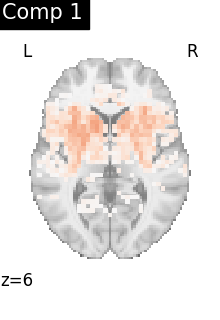

One plot of each component

for i, cur_img in enumerate(iter_img(dictlearning_components_img)):

plot_stat_map(

cur_img,

display_mode="z",

title=f"Comp {int(i)}",

cut_coords=1,

vmax=0.1,

vmin=-0.1,

colorbar=False,

)